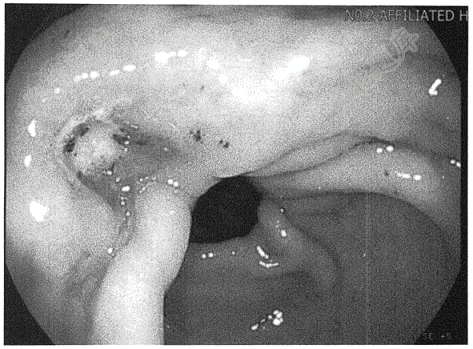

- 单项选择题男,68岁。因“上腹痛1年,解黑便伴头晕3天”入院。长期烟酒史。查体:神志清,颈静脉无充盈,全腹无压痛及反跳痛。入院查胃镜所示如图。考虑诊断( )

A、胃癌伴出血

B、胃溃疡穿孔

C、胃溃疡伴出血

D、胃溃疡伴幽门梗阻

E、急性出血性胃炎